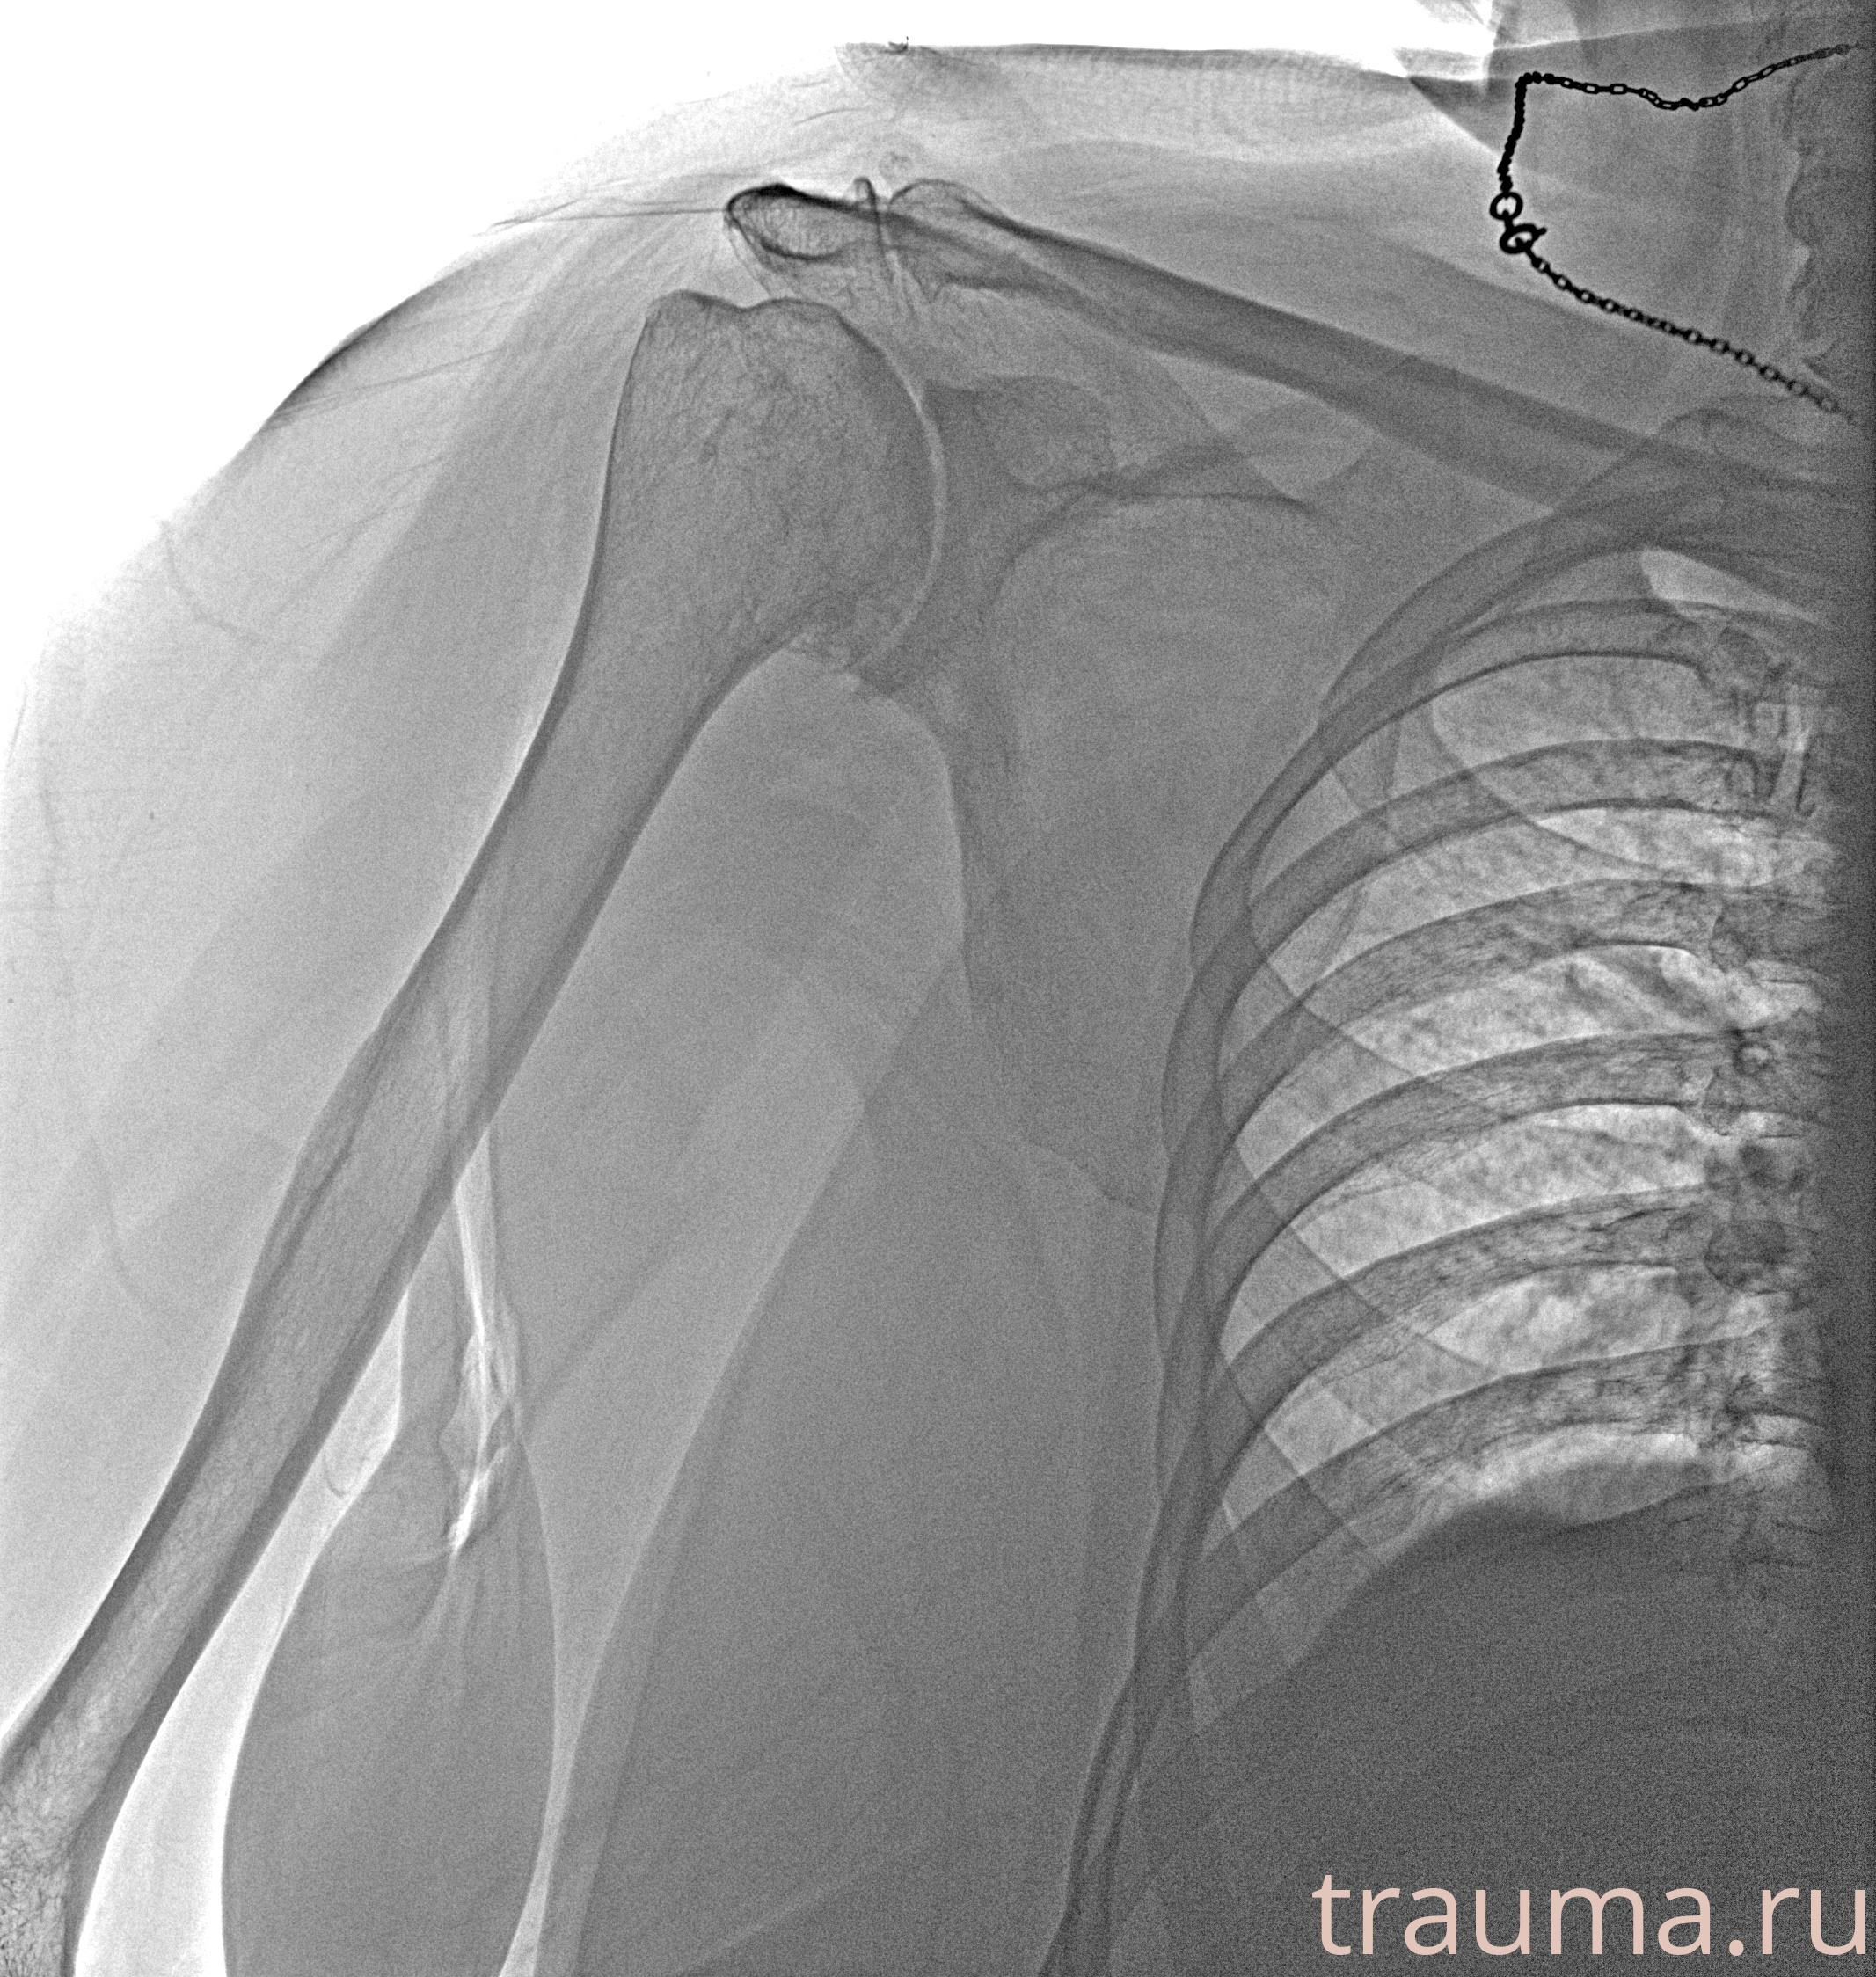

Рентгенограммы

Рентген на дому: по вашему адресу приезжает врач-рентгенолог, травматолог-ортопед с мобильным рентгеновским аппаратом, проводит диагностику травмы или заболевания, делает необходимые рентгенограммы, дает рекомендации по дальнейшему лечению. Получить качественные снимки в домашних условиях возможно благодаря уникальной методике, разработанной МосРентген Центром для института  Склифосовского